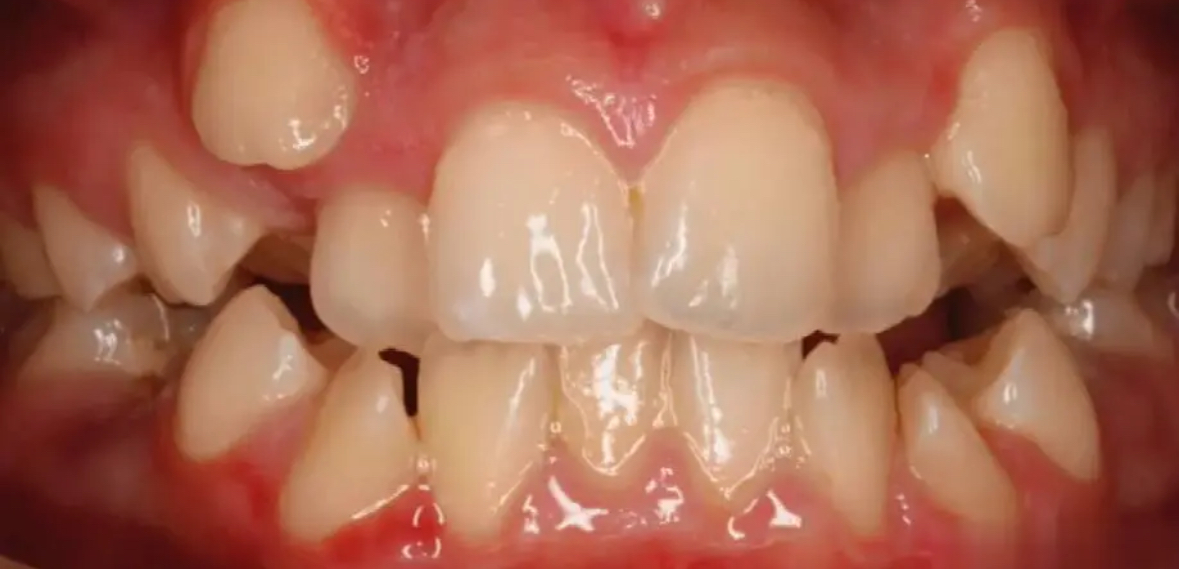

隨著社會對個人形象重視程度的提升,越來越多的成年人開始關注自己的口腔健康和美觀問題。對于那些希望改善牙齒排列不齊狀況的成年人來說,正畸治療成為了一個重要的選擇。然而,成人矯正牙齒面臨一系列獨特的挑戰。珠海六和口腔醫院將探討這些挑戰,并提供相應的解決方案。

成人的牙齒及頜骨發育已經完成,相比青少年時期,牙齒移動更為困難。此外,許多成年人可能還伴有其他口腔問題如齲齒、牙周病等,這使得矯正過程更加復雜。

成人矯正通常需要更長的時間才能看到效果,根據具體情況的不同,整個療程可能持續18個月到3年不等。

挑戰三:外觀顧慮

無論是哪種類型的矯正器具,初期佩戴時都可能會引起不適感,比如口腔潰瘍或者牙齒敏感等問題。